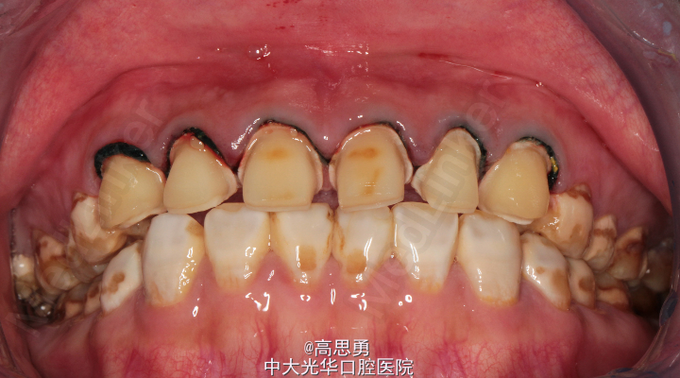

主诉:全口氟斑牙,要求美容修复。 现病史:患者出生并长期生活于广东省朝阳市,自恒牙萌出以来,全口牙表面上有白色、褐色斑块,未做特殊处理,现因自觉严重影响美观,遂到我院修复科要求治疗。 既往史:无心血管病、血液病、无传染病史、无药物过敏史。

检查(包括专科检查及辅助检查):详细记录口腔颌面部检查、牙体检查及牙周检查(附修复前照片,影像学检查图片) 1、全身状况良好,无全身系统性疾病,自主行动能力正常。精神心理状态无异常。 2、颌面部左右对称,面部比例协调,面部正面形态尖圆形。颞下颌关节运动无异常,开口型无异常,颞下颌关节无弹性,无压痛。 3、口内黏膜未见瘢痕,舌运动无异常。唇颊系带附着无异常,唾液分泌无异常。 全口牙表面广泛着色,可见白垩色到茶褐色的斑块,牙体完整,未见明显的实质缺损。牙龈正常,无肿胀无瘘管。

诊断:氟斑牙(着色型、中度) 患者意愿:患者希望尽快解决全口牙颜色改变的问题,不希望接受效果不明确、复诊次数多、维持时间短的治疗方案,可以接受费用较高的治疗方案,希望达到牙齿永久的形态、排列、颜色的尽可能完美的效果,但要求尽量少损伤牙体结构。下颌牙暂时不修复。 治疗方案:全瓷贴面修复,改善前牙美观。